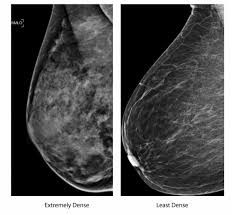

How Does Breast Cancer Look Like In Ultrasound : A A Simple Breast Cyst 75 B Breast Ultrasound Showing A Cancer Download Scientific Diagram / This high amount of echo results in a bright white spot appearing on the ultrasound image.. If your breast tissue is too dense for a mammogram. What does breast cancer look like on a mammogram? Screening mammograms have been used since the 1980s. Ultrasound is not used on its own as a screening test for breast cancer. A breast ultrasound is most often done to find out if a problem found by a mammogram or physical exam of the breast may be a cyst filled with fluid or a solid tumor.

This breast cancer ultrasound image shows changes related to breast cancer that are not seen as microcalcifications or a mass or lump. Any area that does not look like normal tissue is a possible cause for concern. If your breast tissue is too dense for a mammogram. Ultrasound imaging allows better evaluation of the status of the axillary lymph nodes in patients with ibc, an important step in determining extent of disease prior to initiation of chemotherapy. If a solid lump shows on the scan you might need to have. It is the most common cause of cancer death in women. in 2005 alone, 519 000 deaths were recorded due to breast cancer. this means that one in every 100 deaths worldwide and almost one in every 15 cancer deaths were due to breast cancer. With ultrasound, the radiologist will probably be trying to get a sense of the internal texture of the breast lesion and surrounding area. Physical examination and mammogram can be more accurate in some settings. If there are calcifications within the nodular dcis, one may be able to see these on ultrasound as white flecks. The images that a breast ultrasound produces are in black and white. A diagnostic mammogram is used to check for breast cancer when there is a sign or symptom of disease. A breast ultrasound is most often done to find out if a problem found by a mammogram or physical exam of the breast may be a cyst filled with fluid or a solid tumor. To look more closely at a.

A diagnostic mammogram is used to check for breast cancer when there is a sign or symptom of disease.

Other names for this test: Sometimes breast cancer can look like a fibroadenoma and fibroadenomas can look like a cancer on ultrasound. Breast cancer is among the most common causes of cancer deaths today, coming fifth after lung, stomach, liver and colon cancers. If your breast tissue is too dense for a mammogram. Doctors often use them to guide a needle during a biopsy. Rather, the right breast is seen as smaller than the left breast. Sometimes the cancer cells can spread into the nearby lymph nodes. There is a slight increase in the density in the right breast compared with the left. What does the doctor look for on a mammogram? cancer.org. The images that a breast ultrasound produces are in black and white. You might not need any further tests if everything looks normal. A screening mammogram is performed at regular intervals to check for breast cancer in women who have no signs or symptoms of the disease. If a solid lump shows on the scan you might need to have.